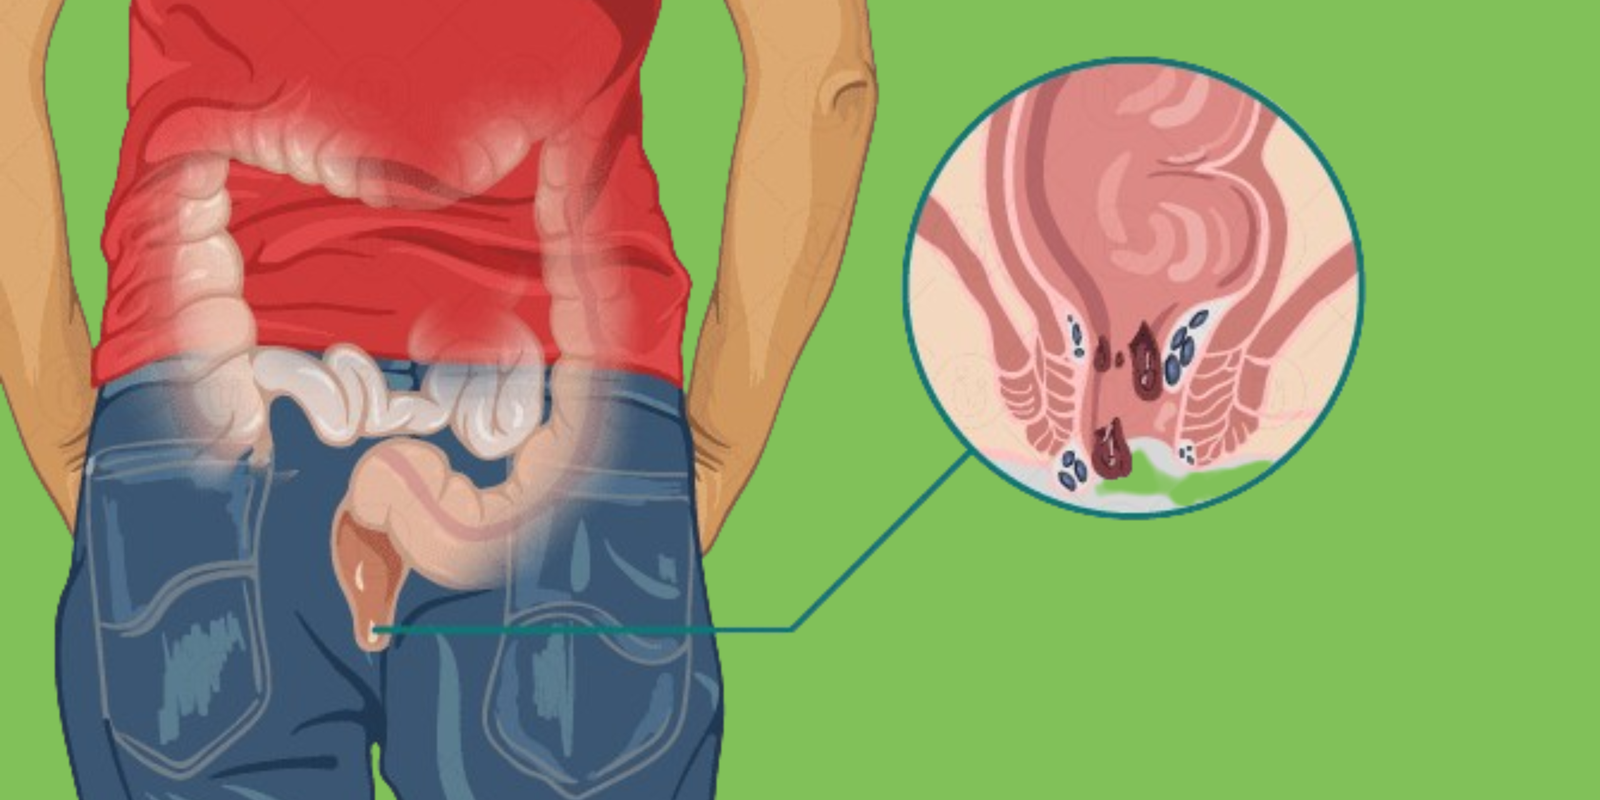

Wasir atau ambeien adalah kondisi pembengkakan pembuluh darah di area anus yang kerap menimbulkan rasa nyeri, gatal, hingga munculnya benjolan yang mengganggu aktivitas sehari-hari.

Banyak penderita wasir yang mengalami kesulitan buang air besar, duduk terlalu lama, bahkan berdarah saat buang air. Kondisi ini perlu penanganan yang tepat dan tidak bisa dibiarkan terlalu lama.

Wasir bisa terjadi akibat berbagai faktor seperti sering mengejan, kebiasaan duduk terlalu lama, kekurangan serat, serta gaya hidup kurang aktif. Gejalanya meliputi rasa panas atau nyeri di anus, keluarnya darah saat buang air besar, hingga benjolan di sekitar anus. Jika tidak segera Anda tangani, wasir bisa berkembang menjadi lebih parah dan mengganggu kualitas hidup.